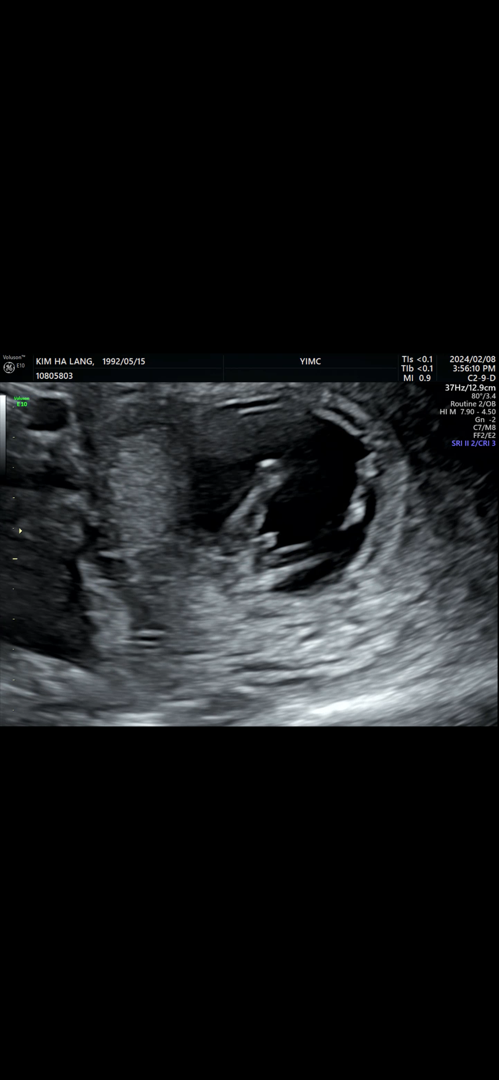

11주5일성별

11주5일 1차 기형가 검사를 하러갔는데요. 이녀석은 셋째. 위에 두아이는 딸이라 처음 보는모습에 살짝 놀라는중에 선생님도 함께 발견하시고 놀라셔서 마음속으로 아들일거라 기대하며 확신하는 중인데.. 들어갈수도있다는 얘기를 많이 듣기도해서요...! ㅠㅠ아들에대한 기대를 품어도될까요??ㅎㅎ